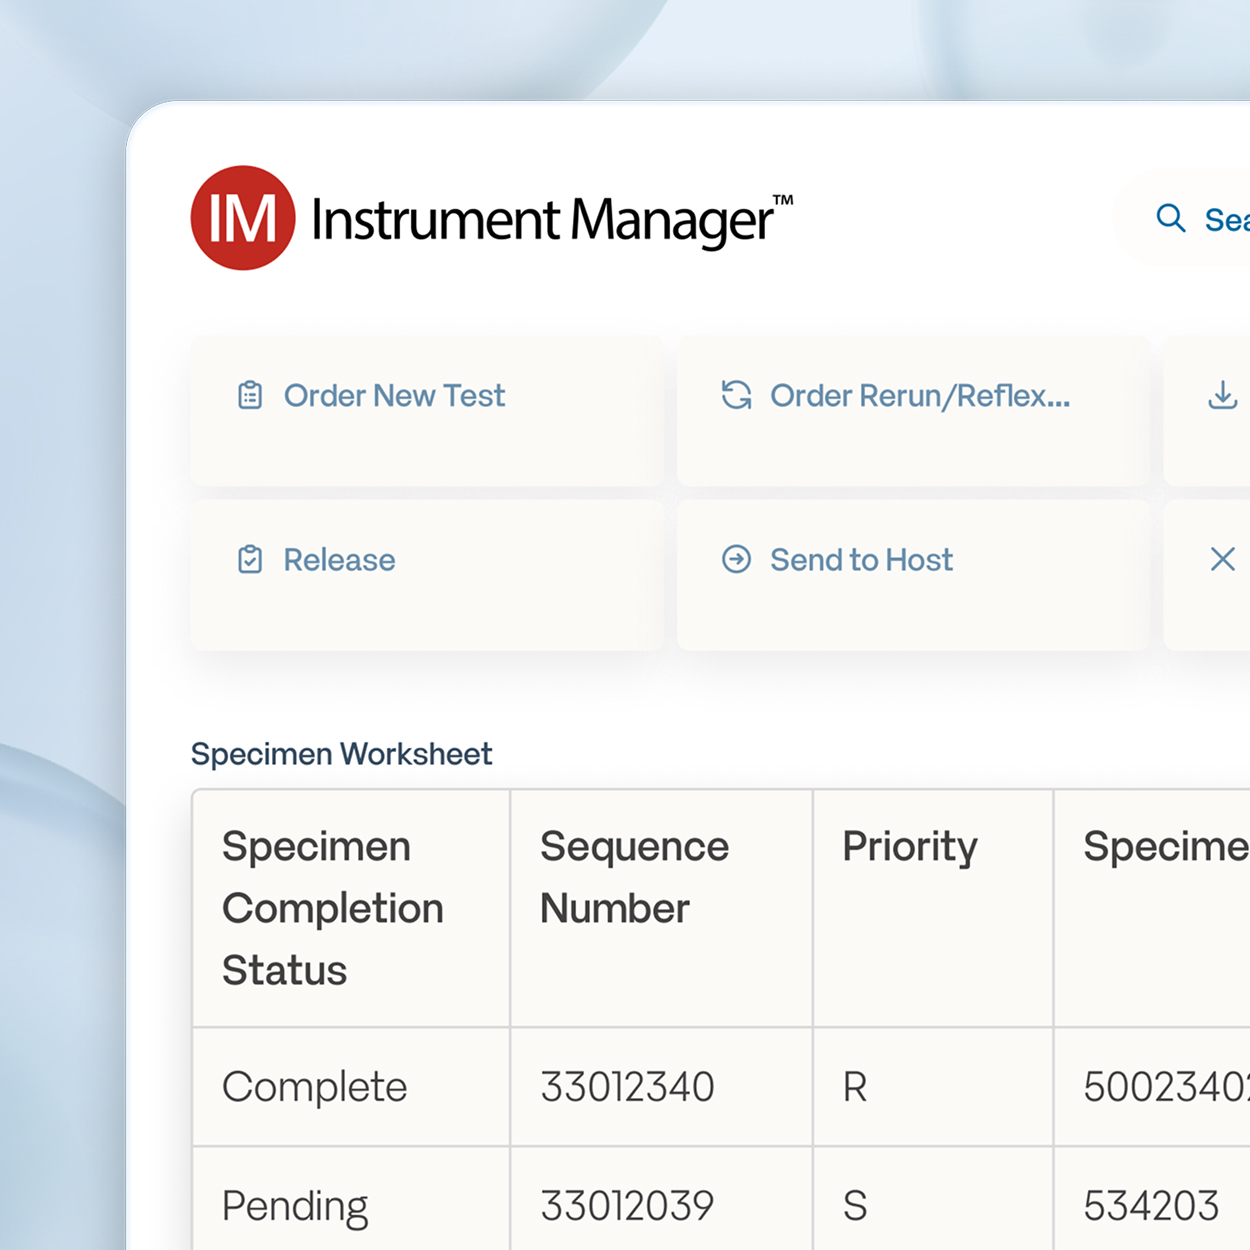

Specimen Management Workspace

The comprehensive Specimen Management workspace enables improved patient care with customizable displays for tracking and reporting results.

- Sort by discipline, instrument, or other metric.

- Color code STAT and high-priority results for escalated review.

- View patient demographics with test results to assist with decision-making.